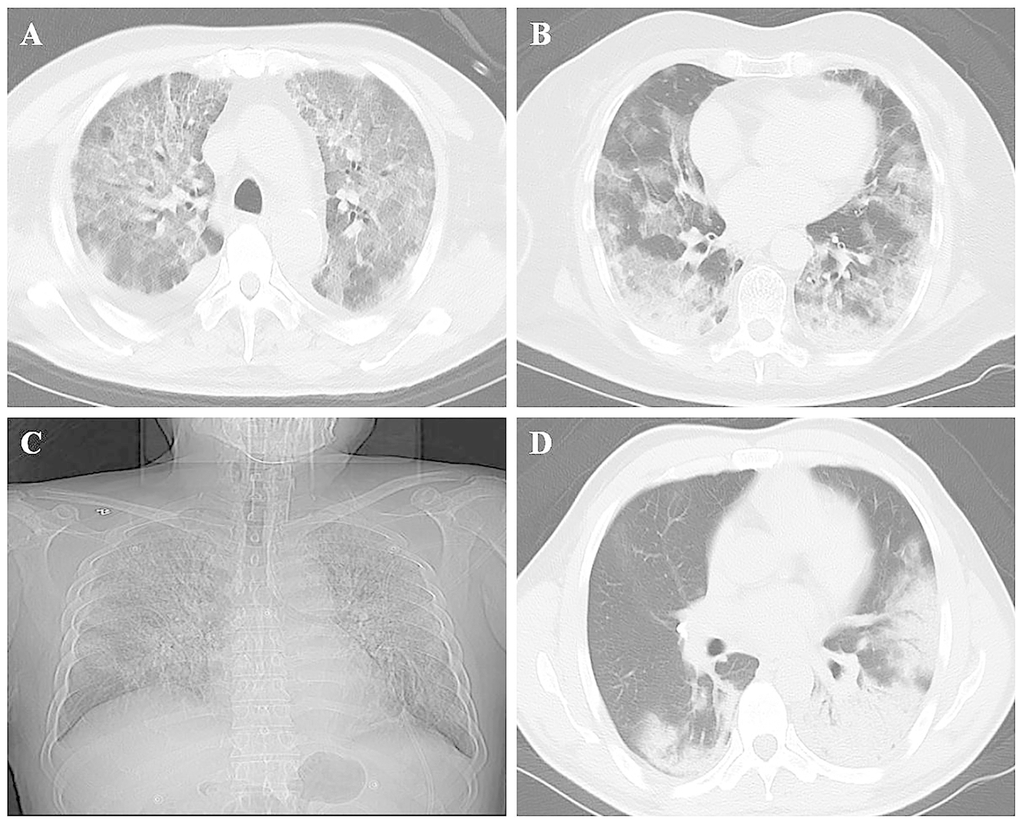

All patients (59/59; 100%) showed abnormal CT findings (Table 3). The main features of the imaging examination were ground-glass opacity (58/59; 98%; Figure 1A), consolidation (37/59; 63%), and ground-glass opacity combined with consolidation (36/59; 61%; Figure 1B). Compared to non-ICU patients, the incidence of consolidation and ground-glass opacity combined with consolidation in ICU patients was higher (73% vs. 33%, P = 0.006; 70% vs. 33%, P = 0.011, respectively). Furthermore, 40/59 (68%) patients showed involvement of all lung lobes in the ICU group (Figure 1C) as compared to the non-ICU patients, whereas the incidence of all lung lobes (75% vs. 47%, P = 0.043) and the number of lung lobes were higher in patients with ICU (median, 5 [IQR, 5–5] vs. median, 4 [IQR, 2–5], P = 0.012). Among 59 patients with COVID-19, 43 (73%) were multifocal, 15 (25%) were diffuse, and only 1 (2%) was focal. A significant difference was detected in the degree of lung involvement between ICU and non-ICU patients (P = 0.032). Furthermore, 23 (39%) patients had abnormal density shadows around the bronchi: 21/44 (48%) ICU patients and 2/15 (13%) non-ICU patients. The incidence of bronchovascular involvement in ICU patients was significantly higher than that in non-ICU patients (48% vs. 13%, P = 0.040), which might be observed by breathing difficulty and need for mechanical ventilation (Figure 1D). Unilateral or bilateral pleural effusion occurred in 7/59 (12%) patients: 6 in the ICU group (6/44, 14%) and 1 in the non-ICU group (1/15, 7%). In addition, mediastinal lymphadenopathy (short axis, >1 cm) was observed in 13 of 59 patients (22%), fibrous cord shadow in 22 (37%), and arterial plaque in 32 (54%).

Figure 1. Chest imaging of patients with COVID-19. (A) Ground-glass opacity; (B) Lesion with ground-glass opacity and consolidation; (C) Lesion involving all lung lobes of both lungs; (D) Lesion involving the surrounding area of the bronchial blood vessel.